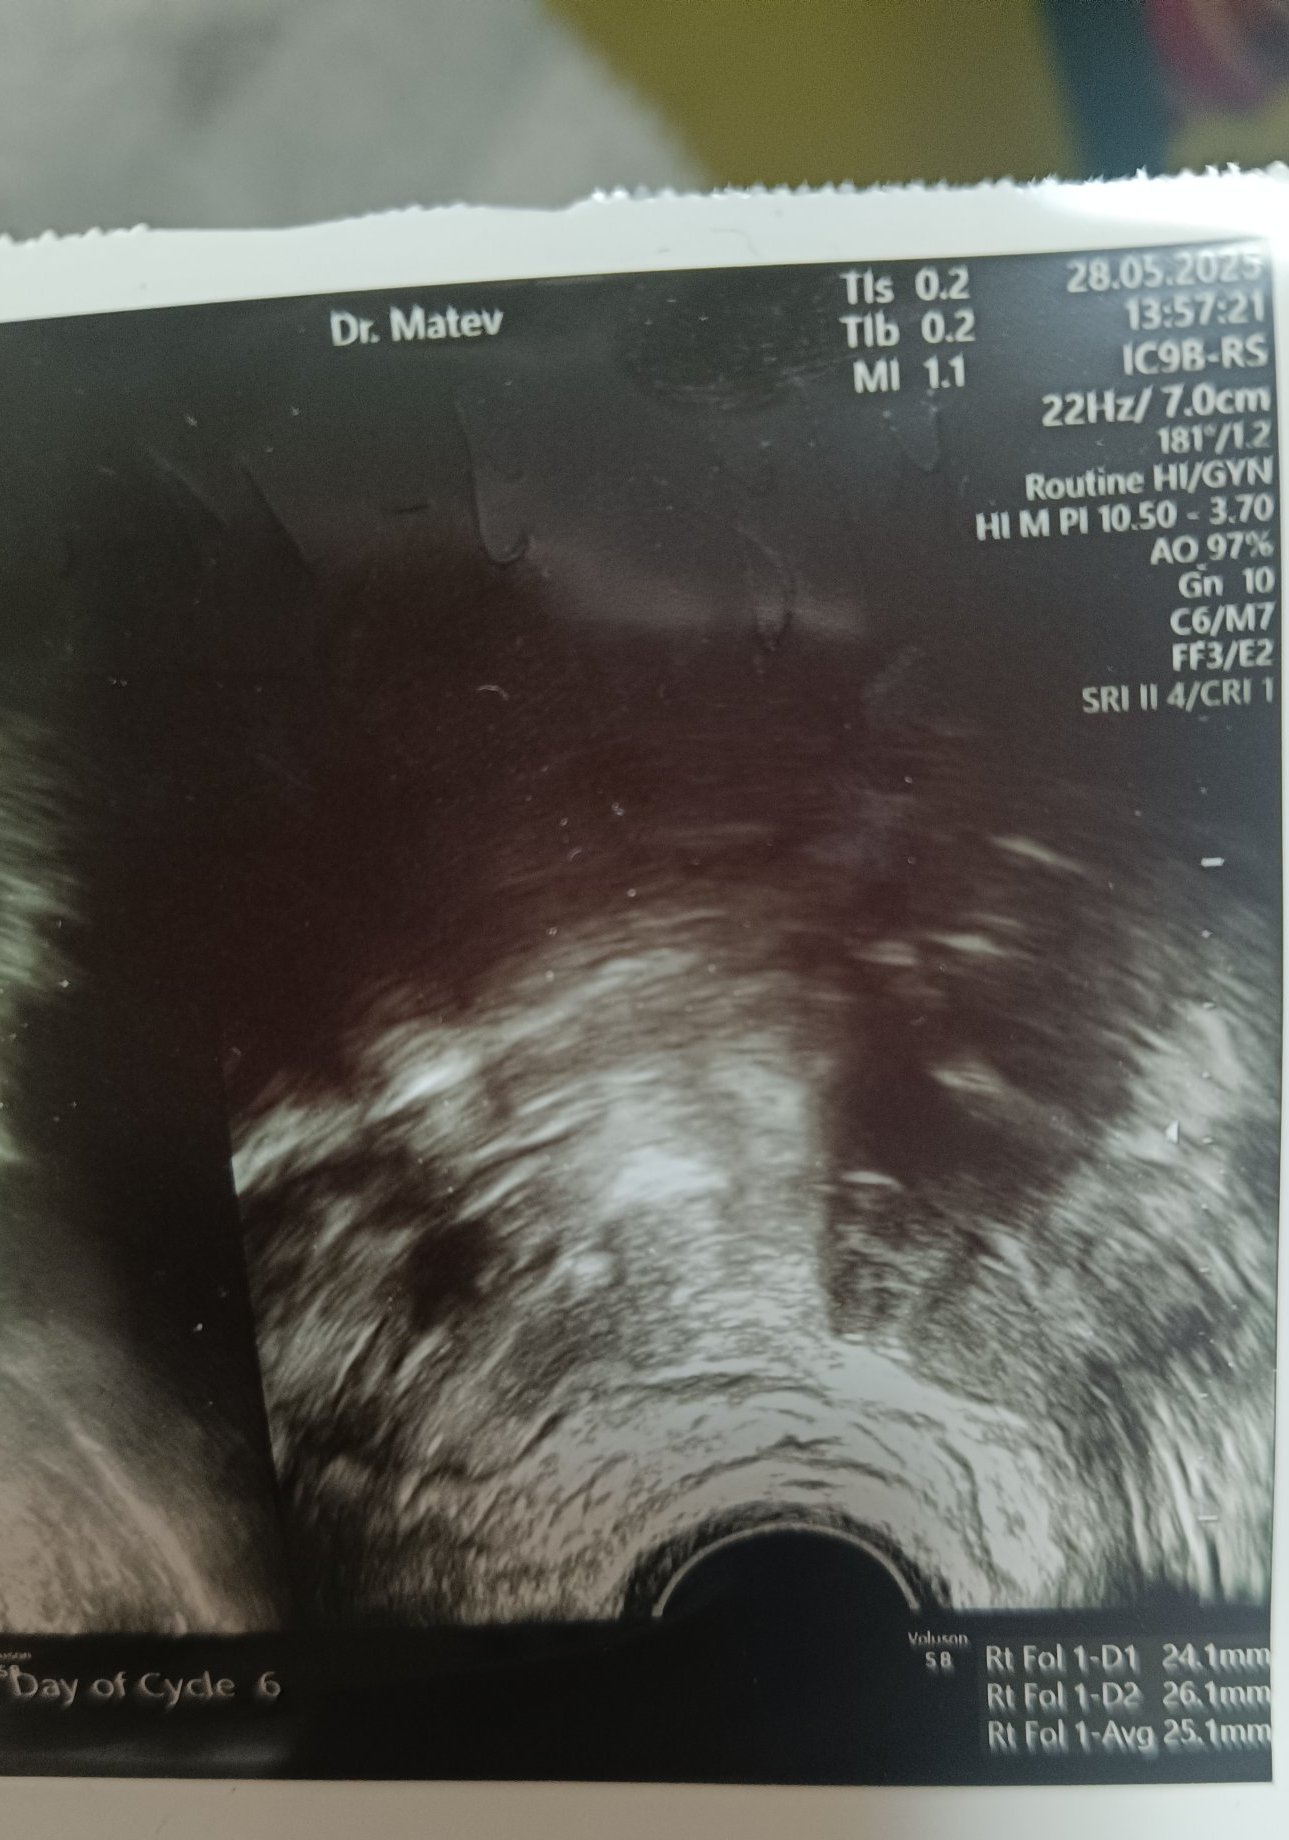

Това е снимката на фоликула.

На снимката нищо не виждам, но на база информация - трябва да е фоликул в дясно, Д1 и Д2 са размери, а това AVG - трябва да е среден размер - 25,1мм и това си е голям фоликул, който трябва да се спука всеки момент... ако не се спука се превръща в ЗФ.

Защо на снимката е посочено 6 ден от МЦ? Нещо не се връзва? На 6-ти ден от МЦ, ако има Ф. с такива размери, това е ЗФ.

Ако е имало вече О., няма как теста за О. да е положителен, защото пика на ЛХ е минал.(той е преди О. - 12 до 48часа)